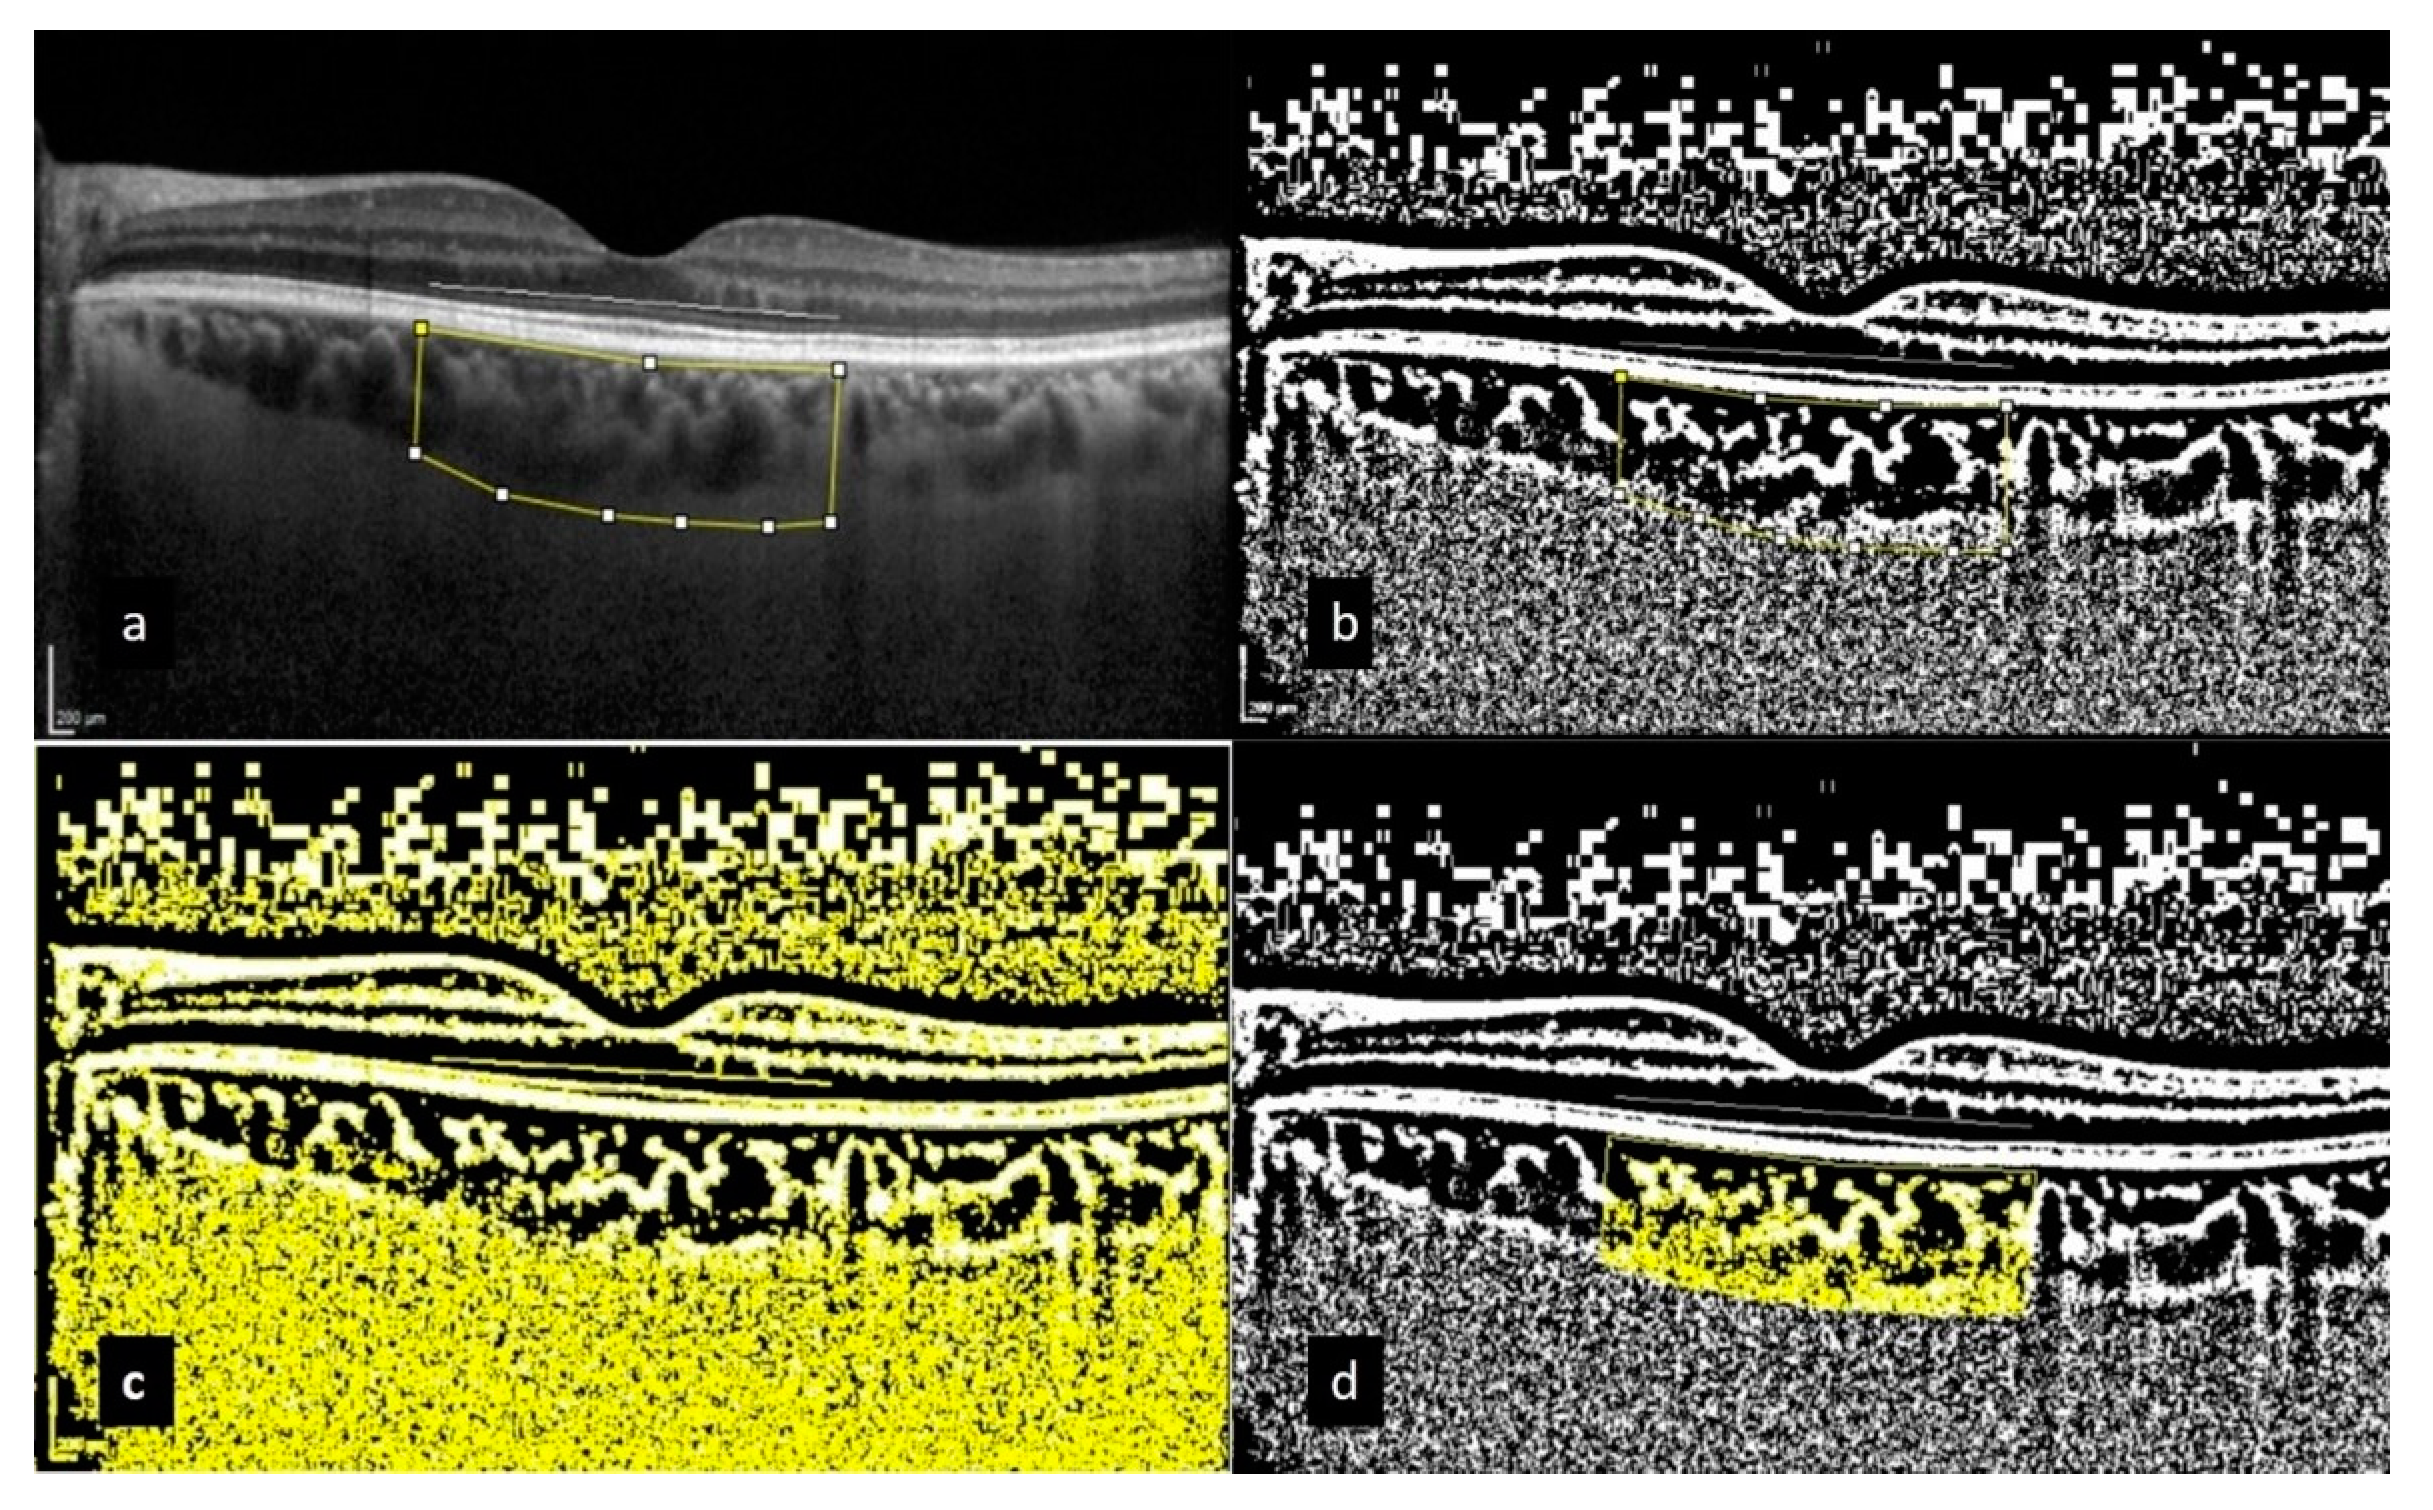

For the precise measurements of ChT, we utilized a high-fidelity precision caliper supplied by EDI-OCT, a renowned tool in ocular diagnostic imaging. This technique enabled a detailed assessment of the perpendicular distance between the hyperreflective outer border of the retinal pigment epithelium and the Bruch membrane layer. Measurements were carefully taken at five critical points along a horizontal scan line, directly at the subfoveal region, as well as at points 500 μm and 1500 μm both temporally and nasally from the fovea (Figure 2). To ensure the highest level of accuracy and consistency, if any single measurement demonstrated a deviation exceeding 10%, we promptly conducted a second round of measurements to verify the results and maintain data integrity.

Within our analysis of the choroidal area (CA), we conducted comprehensive measurements over a total area of 3000 μm, including a margin of 1500 μm extending both nasally and temporally from the center of the fovea. This meticulous vertical measurement extended from the retinal pigment epithelium (RPE) down to the choroidoscleral border, allowing for an in-depth evaluation of the choroidal vascular structure. We identified the edges of the CA using the ImageJ Region of Interest (ROI) Manager (Version 1.50a; National Institutes of Health, Bethesda, MD, USA), a sophisticated software tool designed for precise image analysis. Following this step, we applied binarization through the advanced Niblack auto-local threshold method to enhance image clarity by categorizing pixel intensity. In the processed binarized image, darker pixel areas signified vascular channels, referred to as the luminal area (LA), while lighter pixel areas indicated the stroma of the choroid, termed the stromal area (SA). The CVI was subsequently calculated as the ratio of LA to the total CA, providing invaluable insights into the vascular health and structural integrity within the choroid (Figure 3).

Figure 2. These pictures show choroidal thicknesses obtained at 5 different points (subfoveal, nasal 500 µm, temporal 500 µm, nasal 1500 µm, temporal 1500 µm).

Figure 3. The choroidal vascularity index (CVI) is calculated through the binarization of enhanced-depth imaging (EDI) spectral-domain optical coherence tomography (SD-OCT) images. The process involves (a) tracing the choroidal boundaries to determine the total choroidal area (highlighted with yellow lines); (b) binarizing the image using Niblack’s auto-local threshold method; (c) using the color threshold tool to identify dark pixels, which represent the luminal area; and (d) calculating the CVI by dividing the luminal area by the total choroidal area, covering a 3000 µm region.